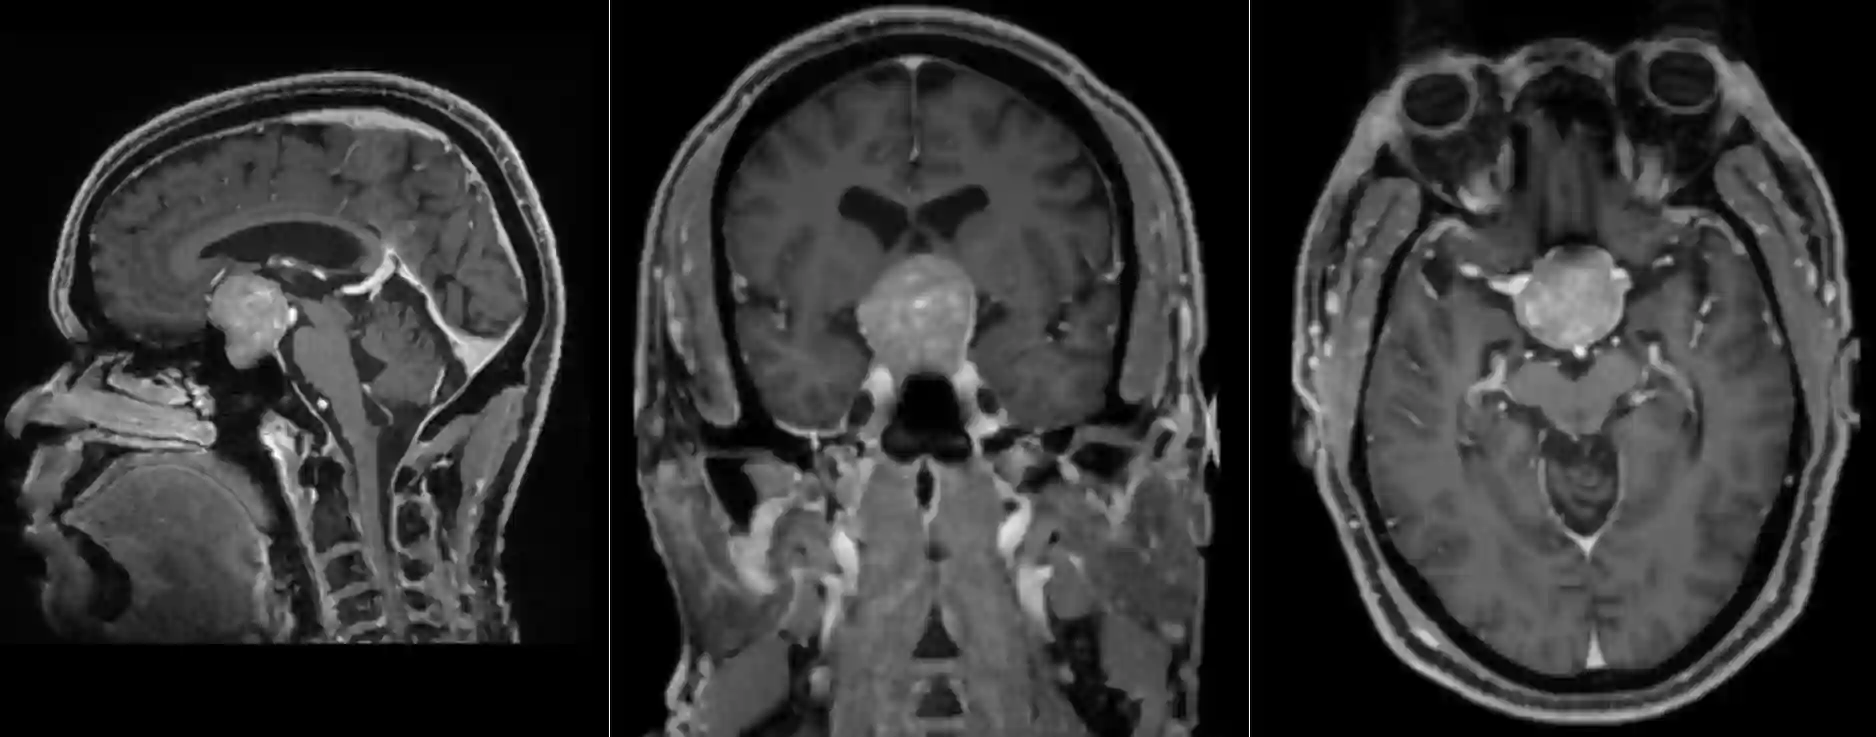

Bildgebung

MRT

Der Goldstandard zur bildgebenden Diagnostik von Hypophysenadenome ist die MRT Bildgebung.